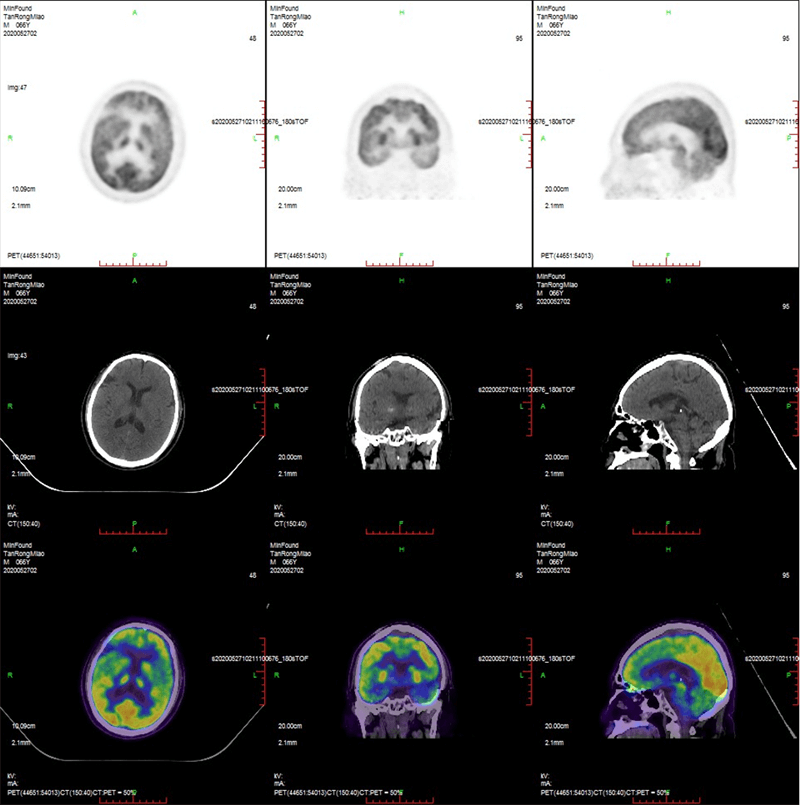

1675935335.png